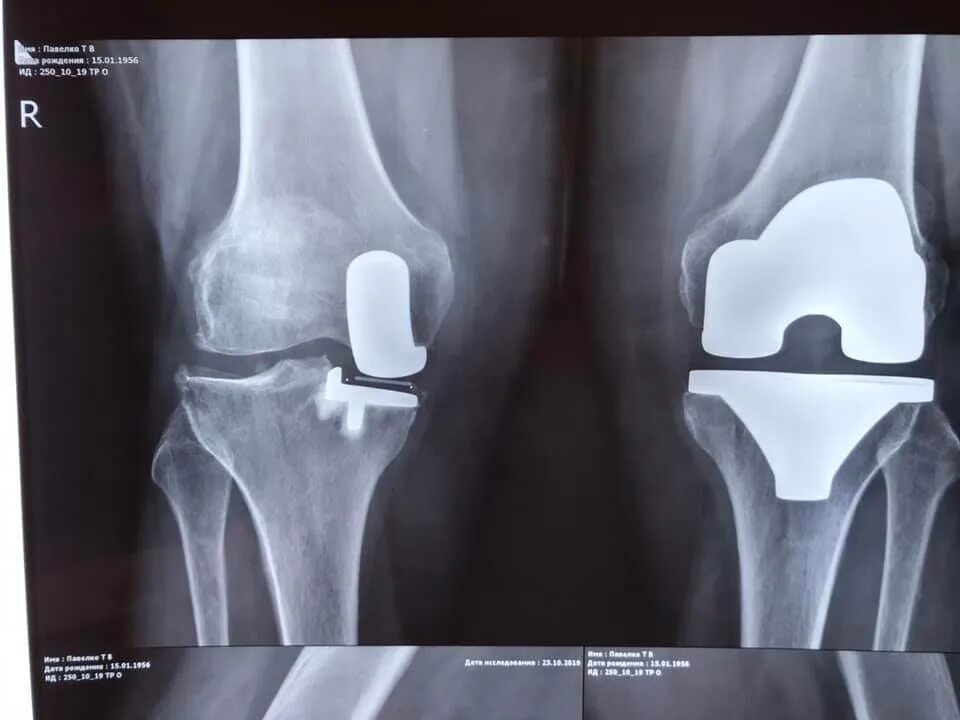

Как делают замену коленного сустава